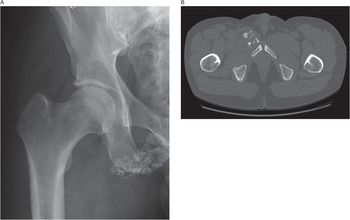

Diagnosing bone disease (Chapter 1) - Pathology of Bone and, Knee Joint Xray Or Mri Doctor Pointed On Area Of Knee Joint,

Knee Joint Xray Or Mri Doctor Pointed On Area Of Knee Joint, Diagnosing bone disease (Chapter 1) - Pathology of Bone and,